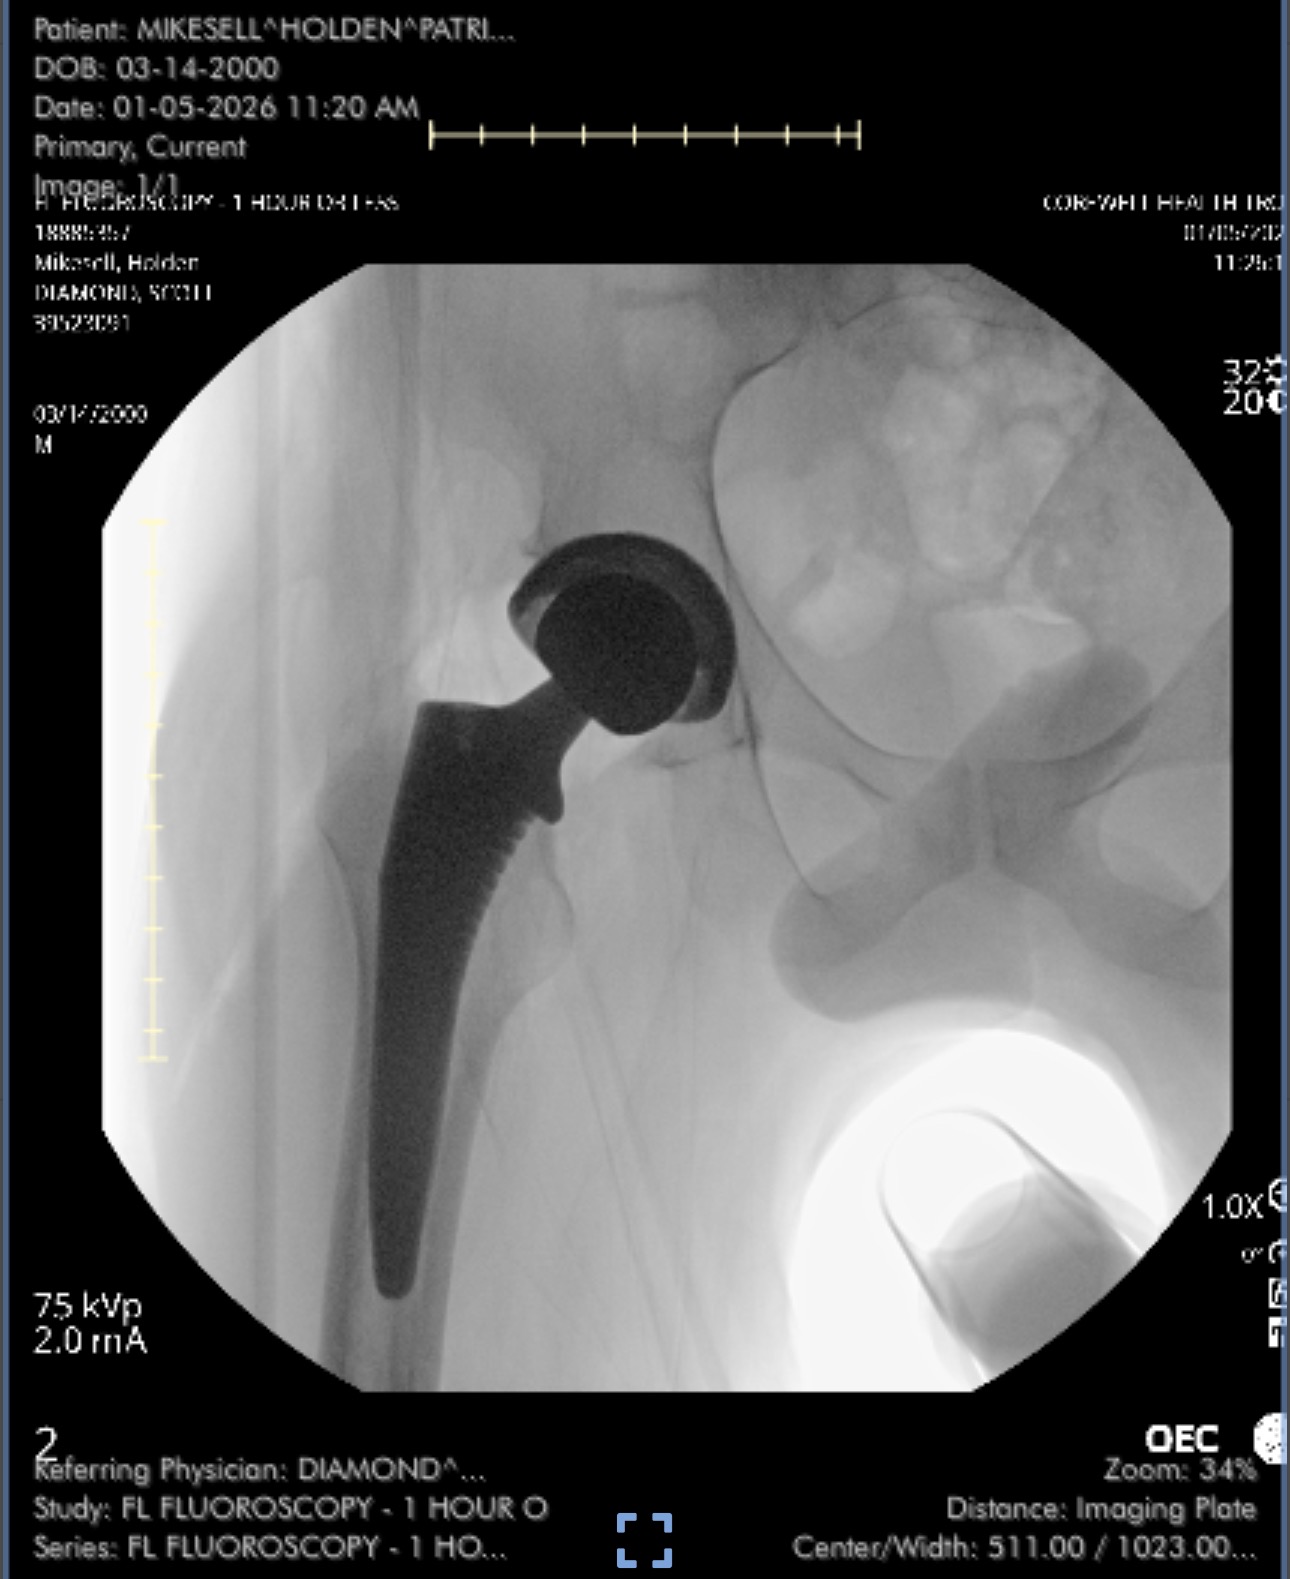

Hello! My name is Holden. I’m 25 years old. For 2 years I had chronic pain and a limp and doctors couldn’t figure out what was wrong. 2 months ago, I was diagnosed with Avascular Necrosis and just had my first hip replacement surgery on Monday, January 5th, 2026. I am getting married on February 6th, 2026. I then have to get my other hip replacement surgery at the beginning of March.